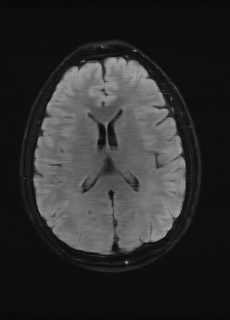

We employ two datasets. The first one is a privately collected, k-space raw data of three sequences (T1subscript𝑇1T_{1}, T2subscript𝑇2T_{2}, FLAIR) from 20 patients, with each sequence containing 18 slices. The sequences are co-registered and taken with an MRI machine with 8 channels; in order to augment training, we treat each channel as an individual image to result in a total of 2,880 three-sequence images, which are divided into a ratio of 17:1:2 for training, validation, and testing. We refer to this dataset as “real data”. In order to further validate our research, we also employ the Brain Tumor Image Segmentation (BraTS) dataset [15, 16], which contains T1subscript𝑇1T_{1}, T2subscript𝑇2T_{2}, and FLAIR. The sequence are co-registered to the same anatomical template, skull-stripped, and interpolated to the same resolution. We divide the selected 167 cases into a ratio of 140:10:17 for training, validation, and testing. From every case, we select the middle 60 slices that contain most of the anatomical details. Because BraTS does not provide raw k-space data, we follow common practices [12, 9] to simulate k-space data. We refer to this dataset as “simulated data”. Below, our insights are first demonstrated with experiments on real data and are further validated on simulated data.